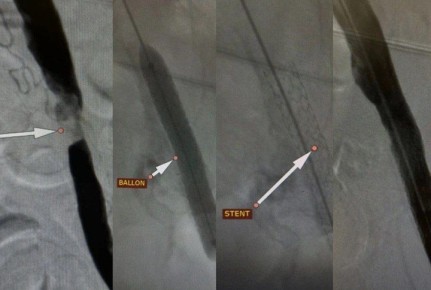

53-летний мужчина поступил к врачам с ужасными болями и критическим нарушением кровообращения в ноге. Диагноз был неутешительным — без срочной помощи его ждала ампутация.Но наши хирурги не сдались. Они провели...